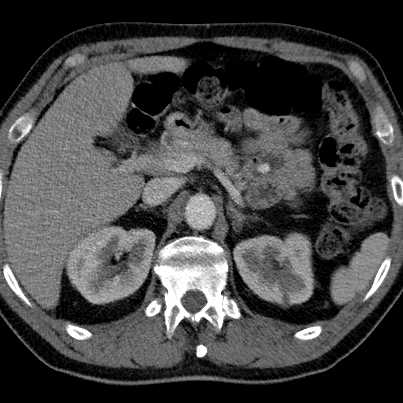

Jejunal hyperdensity

Routine CT shows focal increased density in jejunum, in patient who presented with LUQ pain, diffrential includes enhancing mass and acute bleed.

Virtual non-contrast shows corresponding hyperdensity, consistent with ingested medication. No further work-up needed.